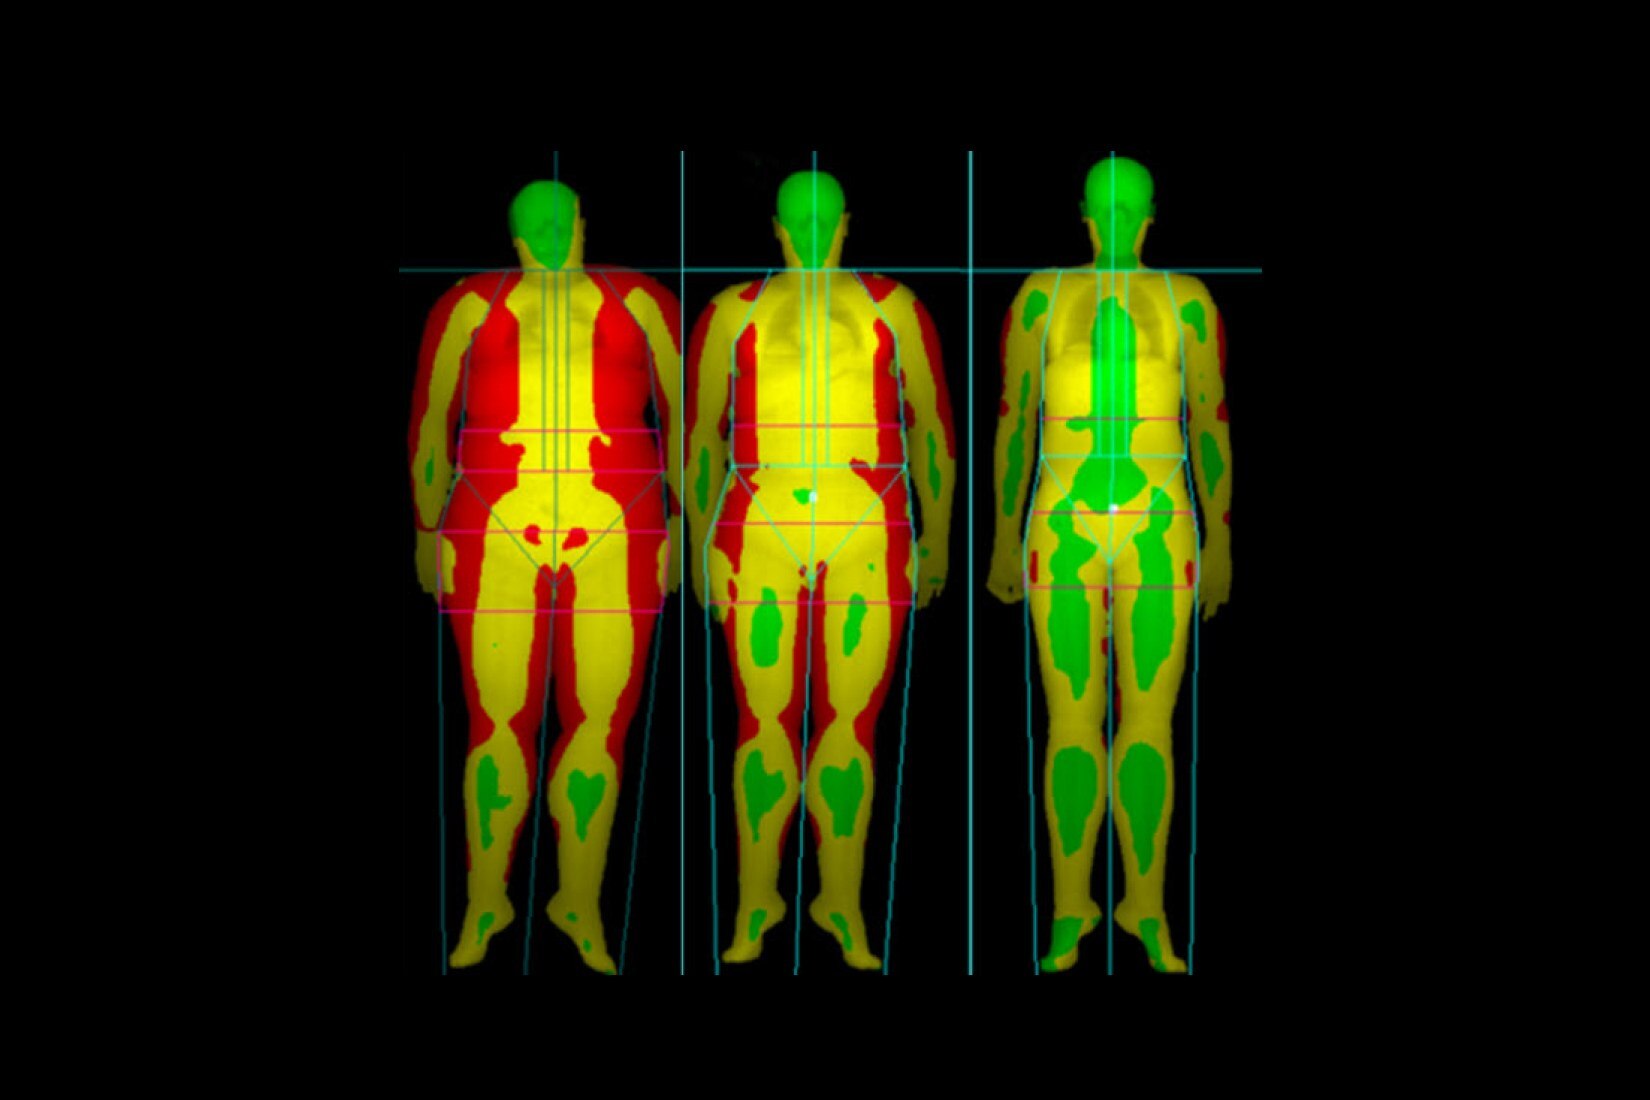

BT deneyiminin en çok zaman alan kısmı taramanın kendisi değil; hastayı hazırlama, rekonstrüksiyon ve raporlama süresi gibi taramanın dışında kalan adımlardır. BT deneyimindeki tüm tarama öncesi ve tarama sonrası adımları analiz ettik ve önemli bulgularımızı Revolution Ascend'in tasarımına dahil ettik. Bu tasarımının sonucunda Revolution Ascend, yüksek BMI değerine sahip hastaları ve girişimsel prosedürleri verimli bir şekilde yönetebilme gibi yaygın endişeleri ortadan kaldırır. Ayrıca, tüm görüntüleme modları için kullanımı kolay iki düğmeli tarama sağlar.

Revolution Ascend, önceki nesil GE BT tarayıcılara kıyasla tünelin içindeki hasta alanını1 yüzde 22 artırmak için daha düşük bir masa pozisyonu ile 75 santimetre genişliğindeki yeni bir gantri tasarımını birleştirir. Bu artış, hastalara daha rahat bir BT tarama deneyimi için daha fazla alan sağlar. Bu yeni daha geniş tünel tasarımı ile Revolution Ascend, sınıfının en kısa geometri tasarımıyla en geniş gantri açıklığını sağlayarak1 BT'yi büyük bedenli hastaların yanı sıra daha küçük bir gantriye yerleştirilemeyecek kadar hassas olabilecek travma vakaları için de kullanılabilir hale getirir.